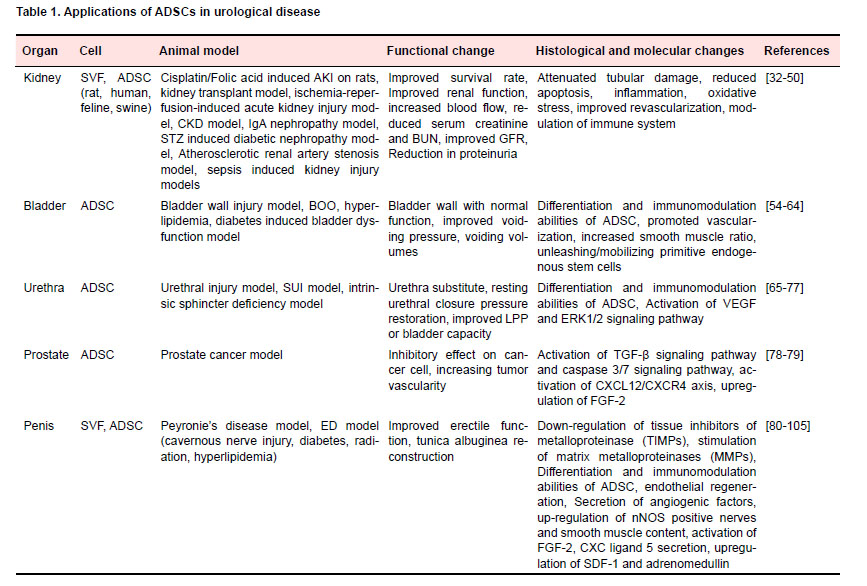

Potential application of adipose tissue-derived stem cells for urological Disease

Abstract 136 | HTML Downloads 51 PDF Downloads 57 | DOI https://doi.org/10.14440/bladder.2014.23Page e2